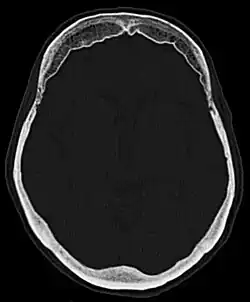

Hyperostosis frontalis at CT

Hyperostosis frontalis interna is a common, benign thickening of the inner side of the frontal bone of the skull. It is found predominantly in women after menopause and is usually asymptomatic. Mostly frequently it is found as an incidental finding discovered during an X-ray or CT scan of the skull.